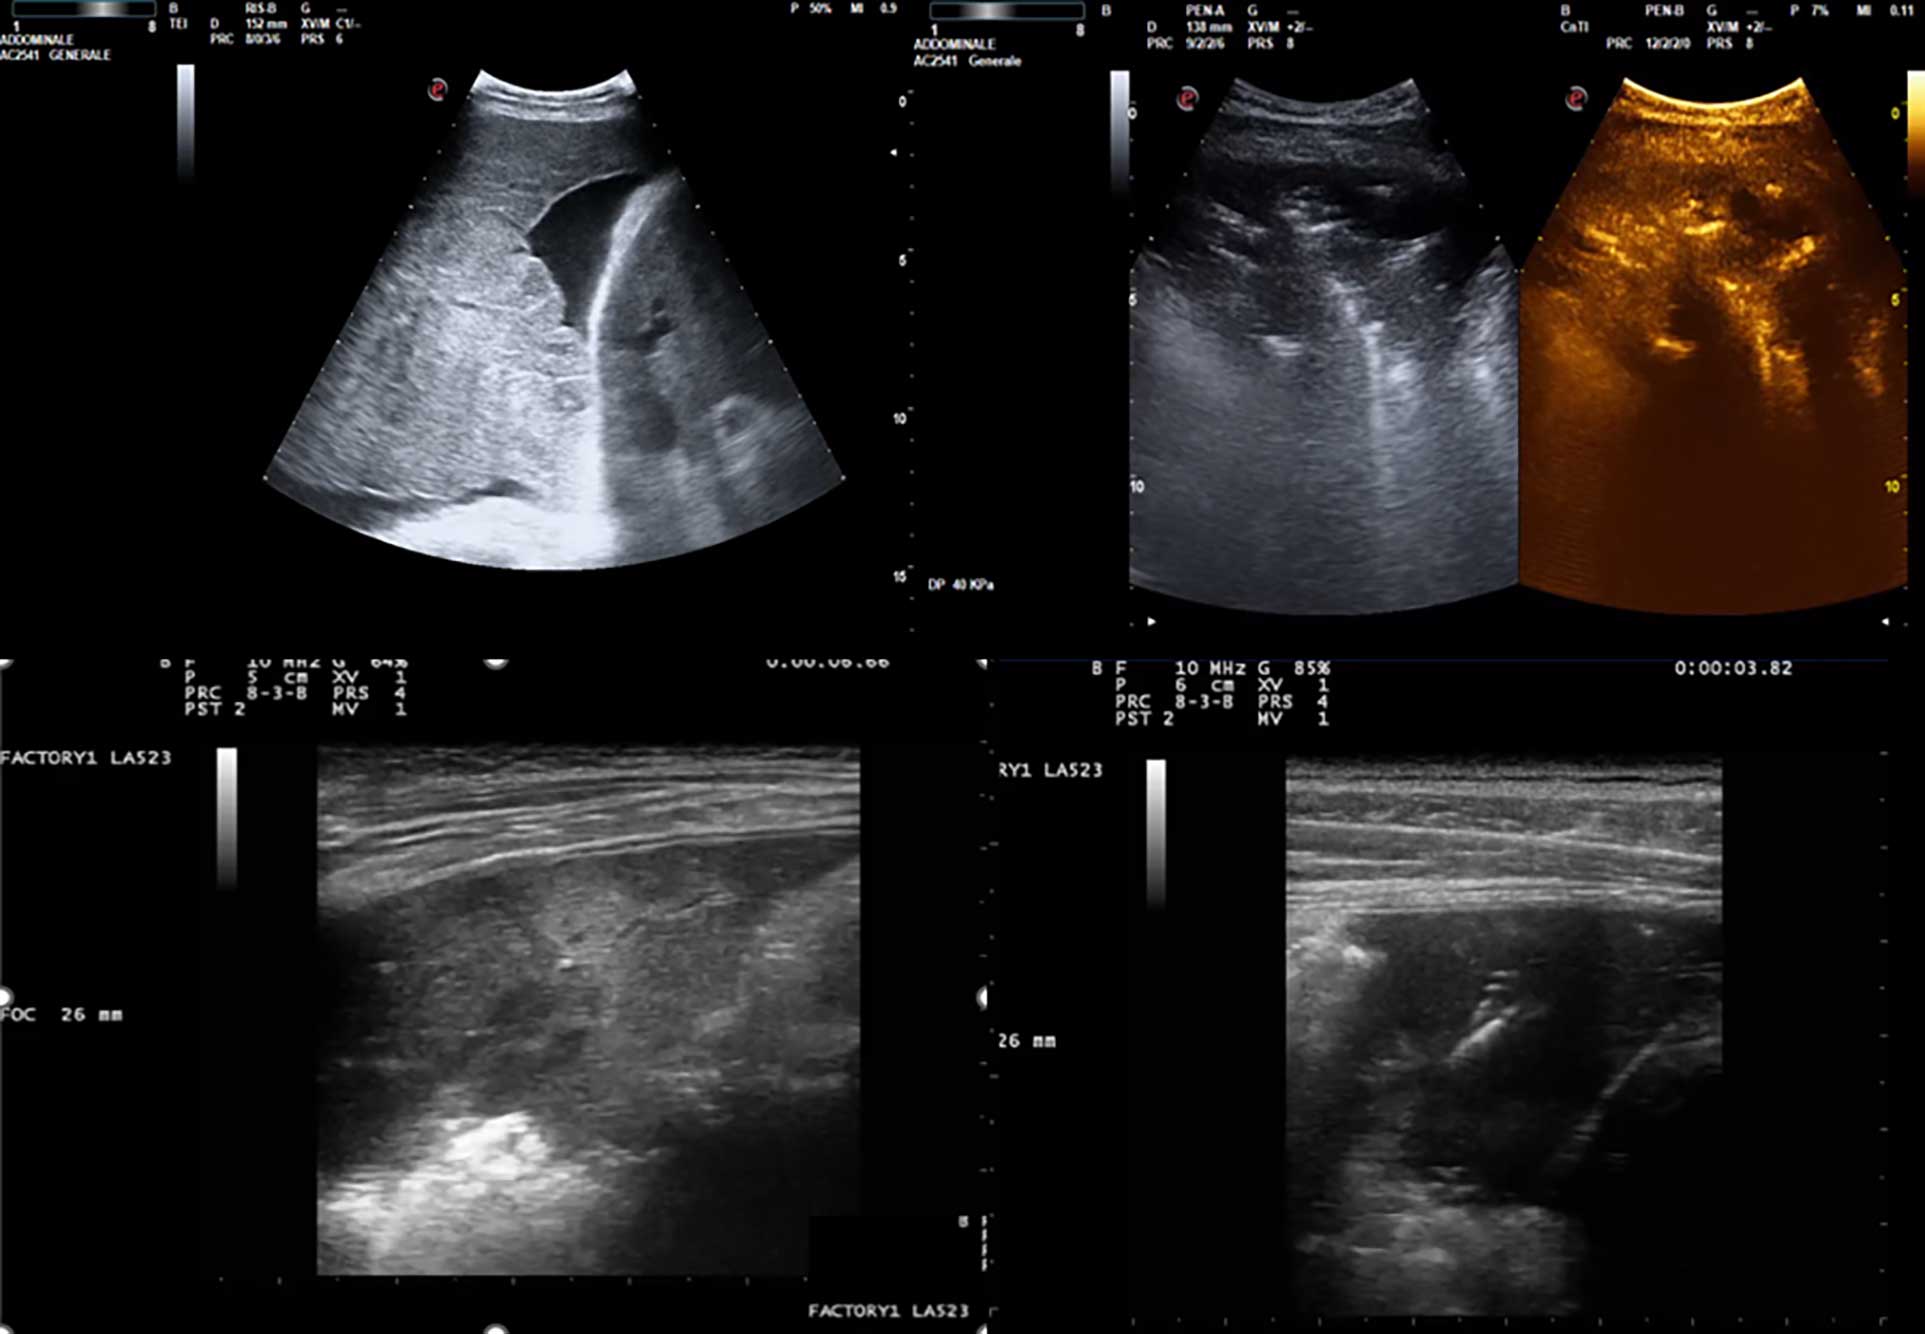

• Pediatric lung ultrasound: Tips and tricks for better scanning and interpretation

Anna Maria Musolino, Laura Gori, Monica Tei, Maria Chiara Supino, Carmen D'Amore, Marta Ciofi degli Atti, Lorenzo Di Sarno, Antonella Amendolea, Alessandro Manganaro, Gino Soldati, Francesco Tursi, Danilo Buonsenso, Cristina De Rose, Renato Cutrera, Marco Cirillo, Paolo Tomà, Caterina Bock, Francesco Esposito, Alberto Villani, Vincenzo Colacino, Annarita Iadecola, Paolo Adamoli, Gian Luca Trobia, Alfina Domenica Coco, Giuseppe Limoli, Rino Agostiniani

1074